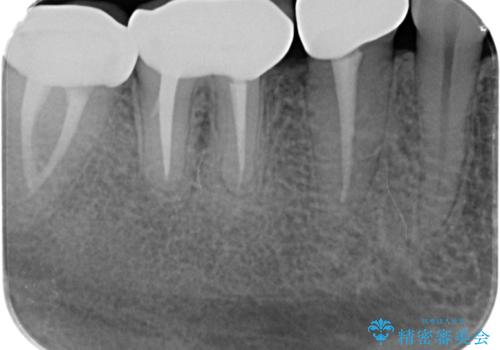

治療途中で長期間放置していたため、歯が歯ぐきから挺出(伸びてくる)してしまい、十分に強度を担保できるセラミッククラウンを装着するスペースが不足した状態です。

加えて、舌の邪魔になっている骨隆起や根尖病変といった問題を歯周外科・精密根管治療を行い、しっかりとスペースを確保したのちセラミッククラウンを作製していきます。